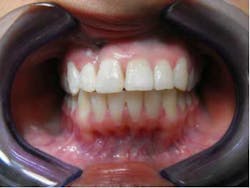

One of my favorite orthodontic cases

This is a case that I took on early in my career as a wannabe orthodontist.

She came to me for an orthodontic consultation. She was 24 years old and hoping to marry her then-boyfriend at some point, but she didn't like her smile; she felt it was unattractive. So we gathered her orthodontic records and pointed out to her that it appeared she had either a supernumerary tooth or over-retained primary tooth between her upper centrals. Along with this, she also had some minor crowding on her lower teeth. She had a Class I molar relationship that I hoped to maintain.